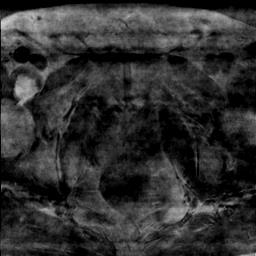

Modern deep neural networks struggle to transfer knowledge and generalize across diverse domains when deployed to real-world applications. Currently, domain generalization (DG) is introduced to learn a universal representation from multiple domains to improve the network generalization ability on unseen domains. However, previous DG methods only focus on the data-level consistency scheme without considering the synergistic regularization among different consistency schemes. In this paper, we present a novel Hierarchical Consistency framework for Domain Generalization (HCDG) by integrating Extrinsic Consistency and Intrinsic Consistency synergistically. Particularly, for the Extrinsic Consistency, we leverage the knowledge across multiple source domains to enforce data-level consistency. To better enhance such consistency, we design a novel Amplitude Gaussian-mixing strategy into Fourier-based data augmentation called DomainUp. For the Intrinsic Consistency, we perform task-level consistency for the same instance under the dual-task scenario. We evaluate the proposed HCDG framework on two medical image segmentation tasks, i.e., optic cup/disc segmentation on fundus images and prostate MRI segmentation. Extensive experimental results manifest the effectiveness and versatility of our HCDG framework.